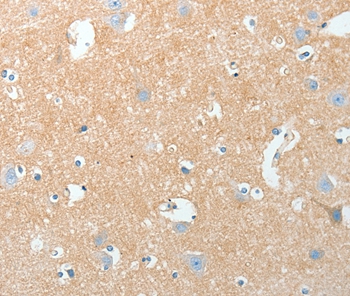

分类: 科研抗体货号: P42783别名: R-PTP-kappa应用: WB,IHC反应种属: Human,Mouse